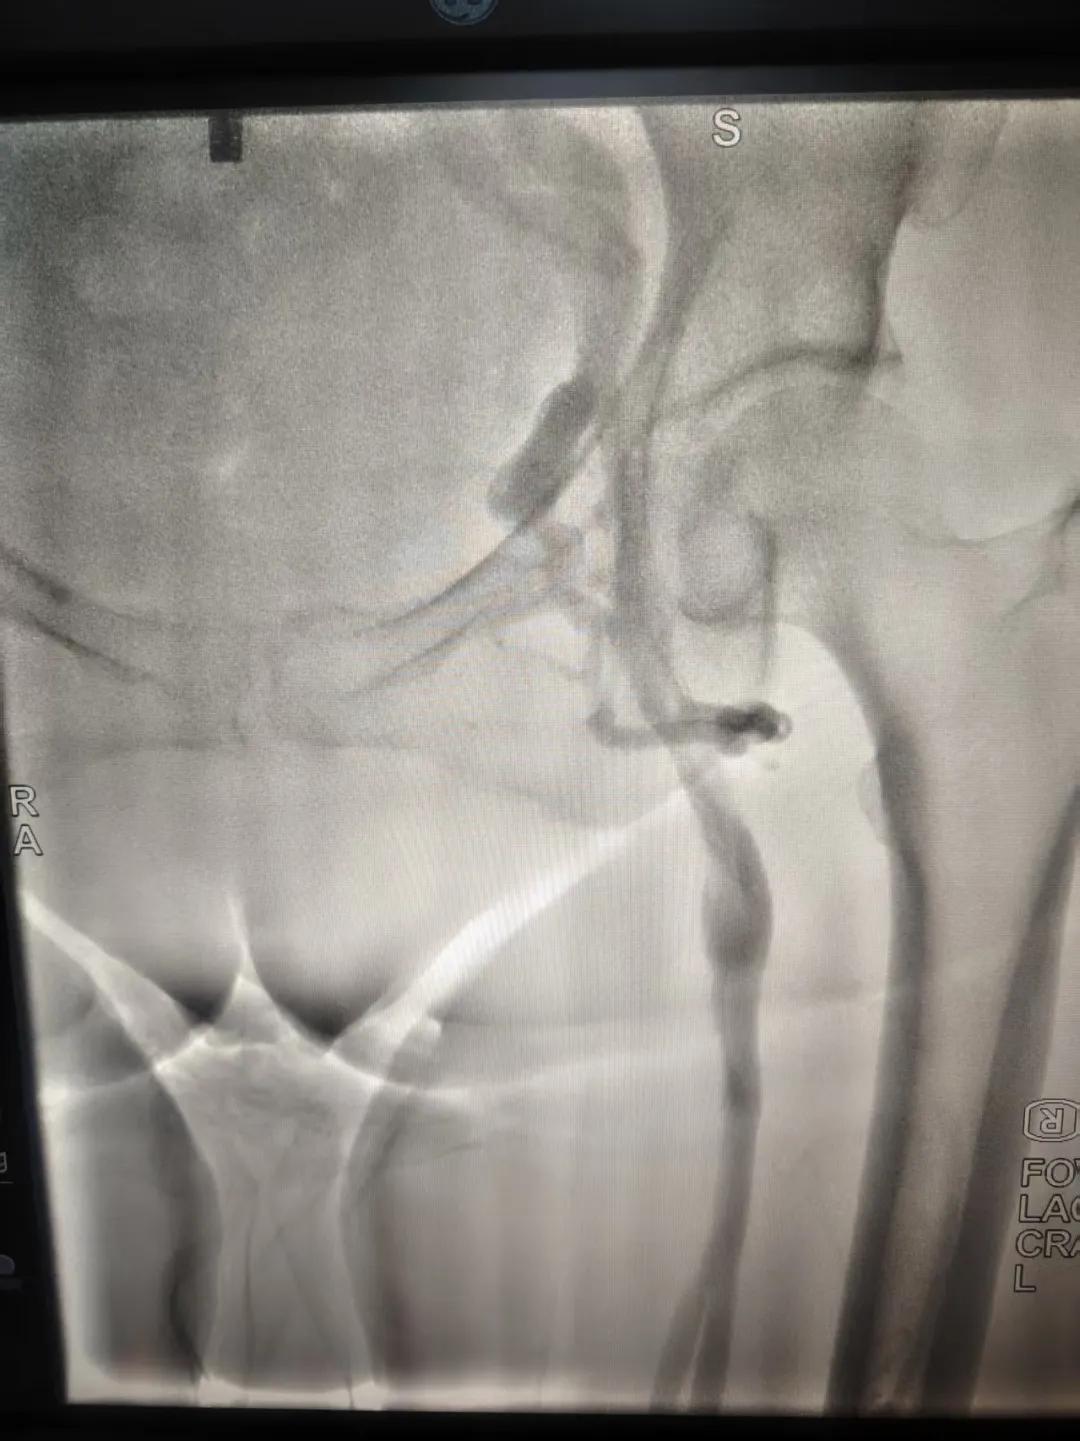

該患者,中年女性,左下肢反復(fù)腫脹、疼痛多年就醫(yī),未明病因。門診就診,經(jīng)血管外科副主任周創(chuàng)業(yè)評(píng)估病情后,為該患者門診行下肢靜脈造影,造影結(jié)果示:左髂靜脈周圍側(cè)枝形成,左髂靜脈壓迫綜合癥。明確診斷后將擇期介入手術(shù)治療。

下肢靜脈造影是診斷下肢靜脈病變(如深靜脈血栓、靜脈曲張、靜脈功能不全等)的“金標(biāo)準(zhǔn)”。靜脈造影可直觀顯示受壓部位、狹窄程度及側(cè)支循環(huán)形成情況,明確診斷與定位,指導(dǎo)治療決策,以及介入治療規(guī)劃,血栓評(píng)估,在復(fù)雜病例或介入治療中造影具有優(yōu)勢。